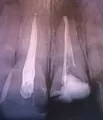

У дочери 13 лет. Вчера сломался зуб, сегодня сделали рентген. Каков будет ваш вердикт? Можно ли будет обойтись без протезирования, а просто поставить штифт?

Комментарий №171744

• В области верхушки корня зуба имеется деструкция костной ткани. Возможно, она появилась вследствие травмы или это снимок ненадлежащего качества. Необходимо понаблюдать за состоянием костей в динамике. Если будут изменения в лучшую сторону, то можно установить штифт и затем провести терапевтическое или ортопедическое восстановление коронковой части зуба.